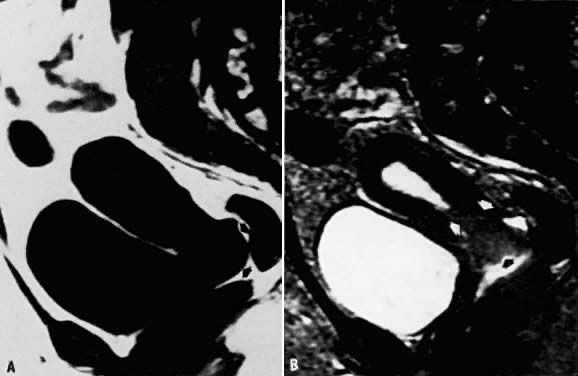

Fig. 14. A. Simple ovarian cyst. Transverse T1-weighted image showing a right adnexal soft-tissue density of low signal intensity ( arrow ). B. With increased T2 weighting, the abnormality shows high signal intensity. The thin wall and the appearance on both T1- and T2-weighted images are consistent with the final diagnosis of a simple ovarian cyst.